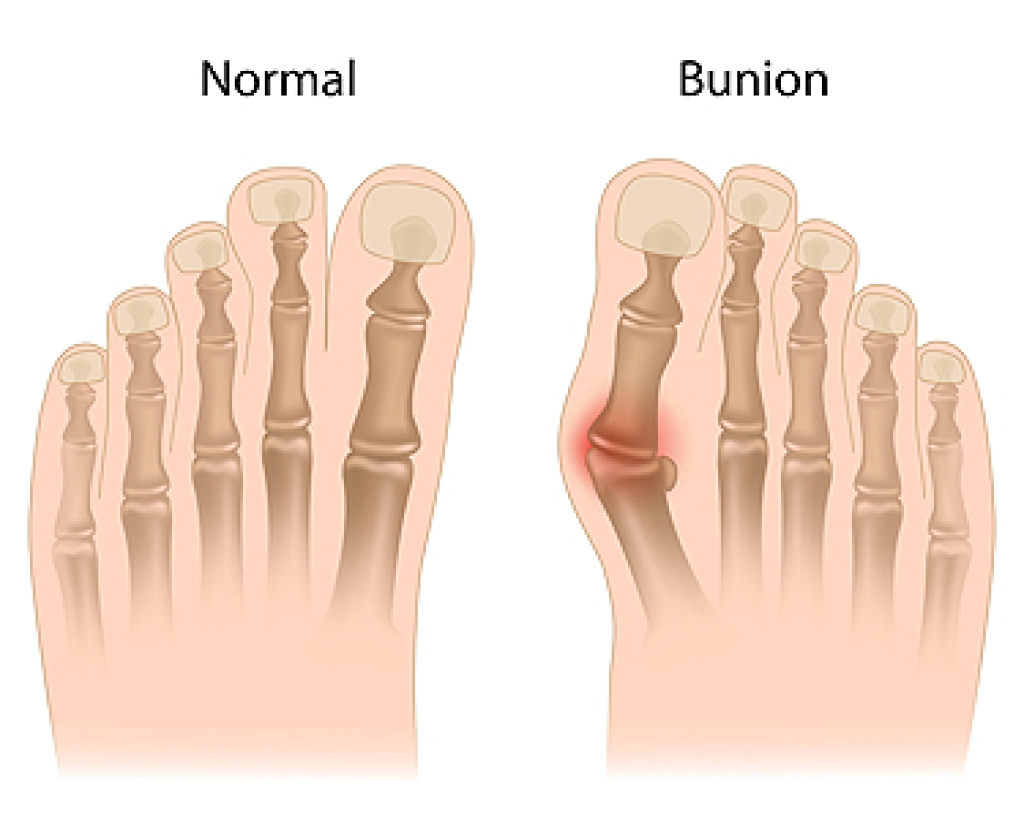

Psoriatic arthritis is a chronic condition that can cause pain, swelling, and stiffness in the feet, often making it difficult to walk or stand for long periods. of time. The inflammation may involve any of the 26 foot bones and ankle joints, as well as their surrounding soft tissues. A common feature of psoriatic arthritis is dactylitis, also called sausage toes, where the entire toe becomes swollen and tender. Heel pain may also occur when the Achilles tendon becomes inflamed, creating symptoms similar to plantar fasciitis. Over time, the toes can curl into claw-like shapes, the big toe may bend upward, or the foot arch may flatten. Skin around the joints may appear red or purple, and stiffness often worsens after periods of rest. A podiatrist can evaluate these symptoms, recommend proper footwear or custom orthotics, and discuss possible surgery if joint damage is severe. If you have foot pain from psoriatic arthritis, it is suggested that you schedule an appointment with a podiatrist for an exam and appropriate treatment.

Arthritis is a joint disorder that involves the inflammation of different joints in your body, such as those in your feet. Arthritis is often caused by a degenerative joint disease and causes mild to severe pain in all affected areas. In addition to this, swelling and stiffness in the affected joints can also be a common symptom of arthritis.